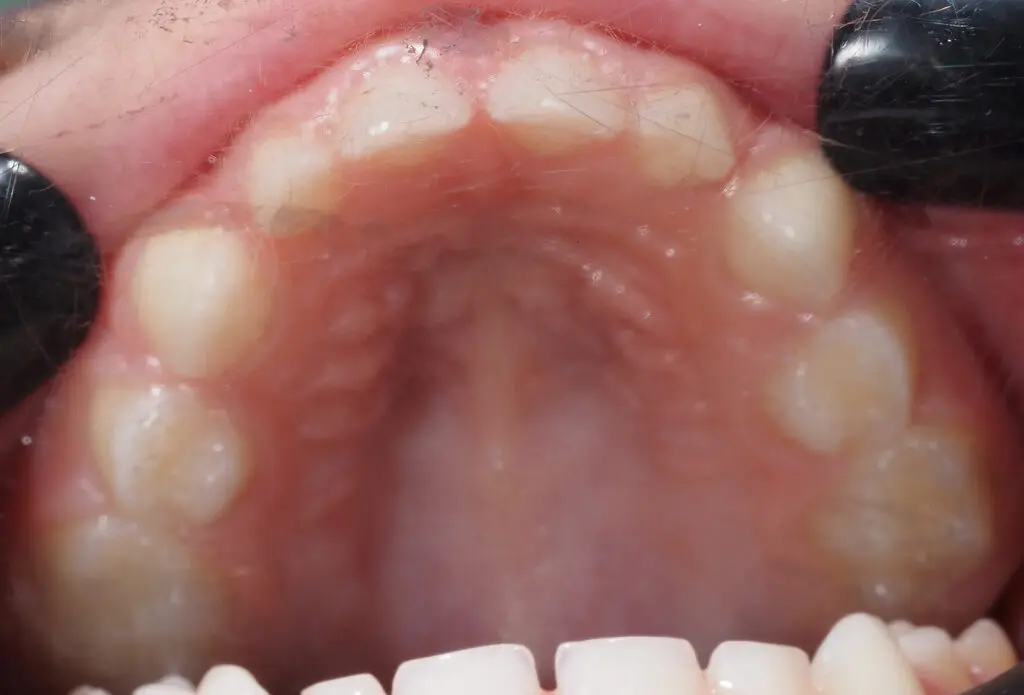

Popatrzmy na kolejne zdjęcie tego samego pacjenta.

To podniebienie. Zdjęcie niewyraźne, bo buzia jest maleńka, i nawet najmniejsze lusterko z trudem się mieści, a dziecku trudno z nim oddychać. Podniebienie jest wąskie i wysokie. Dziecko chodzi do logopedy od 2 lat, cała rodzina dzielnie ćwiczy kobrę, kląskanie i artykulację (albo i nie, bo serio, doba nie jest z gumy, a skoro mowa się poprawia, to chyba tyle wystarczy?) Niestety, język dalej leży na dole płasko jak naleśnik na patelni, buzia ciągle jest otwarta, ale przecież tata też tak ma i żyje, więc o co chodzi?